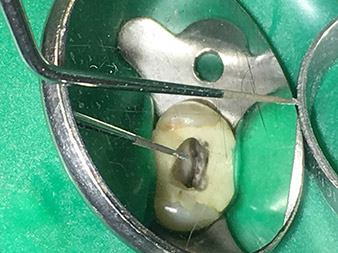

Efficient and atraumatic root canal treatment

Alongside efficient diagnostics and treatment methods, the use of the latest technical aids and instruments also makes an important contribution to successful patient care. Dr Shahrad Nouraie Ashtiani and his team at the practice in Bremen, Germany, treat up to ten endodontics cases a week. Patients’ desires for treatment which is as atraumatic as possible combined with good prognoses for success present a daily challenge for the dentist and oral surgery resident specializing in endodontics.

As an avid user of the expanded W&H instrument range for ultrasonic endodontics, Dr Nouraie Ashtiani is not only able to perform root canal treatments more efficiently but also to do so in a way which puts less strain on the patient. The dental expert masters even the most difficult of situations with ease. In a recent interview, the specialist in endodontics told us about the particular features which characterize the W&H instruments and mentioned possible risks which can arise in root canal treatment.

Dr. Nouraie: Yes, in my opinion. The tips allow you to work in a particularly atraumatic and minimally invasive manner. Among other steps, this applies to the exposure of the individual canal accesses, preparation of the cavity in the area of the pulp chamber, rounding off of the canal openings at the transition from the bottom of the chamber to the root canal and preparation of the coronal regions of the root canals.

It is also possible to activate the rinsing fluid in the root canal system. What’s more, it makes a range of special indications such as the revision of broken-off instruments and root posts possible.